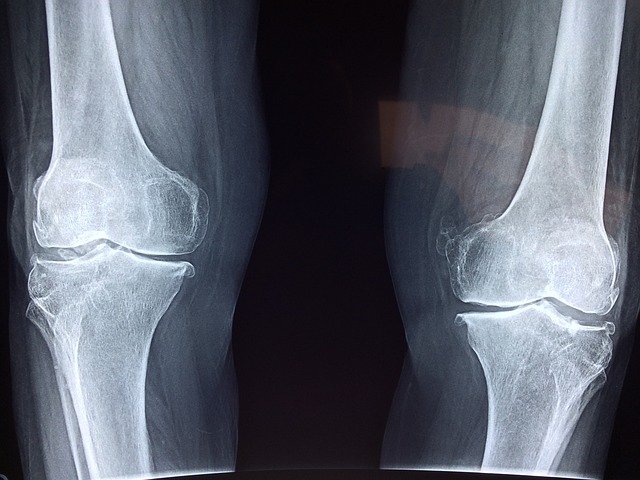

다리 관절

- 엉덩이 관절: 골반과 대퇴골을 연결하는 관절

- 무릎 관절: 대퇴골과 경골을 연결하는 관절

- 발목 관절: 경골, 비골과 발을 연결하는 관절

- 발가락 관절: 발가락 뼈들을 연결하는 관절

무릎 관절

- 콘드로이틴: 연골 재생과 관절 기능 개선

- MSM: 관절 염증 감소와 통증 완화